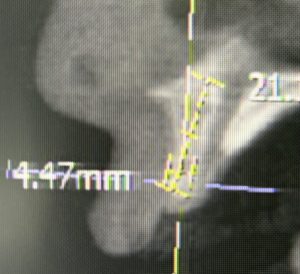

ITインプラントが得意とするのは骨が薄い症例です。特に普通のメーカーでは難しい症例に対して、直径2.2ミリや直径2.8ミリの細いインプラントが使えることです。他のメーカーでは直径3.0ミリが最少となります。

これが何故可能かというと、材質がチタン合金であり通常の純チタンでないので、1.5倍程硬く折れにくいからです。